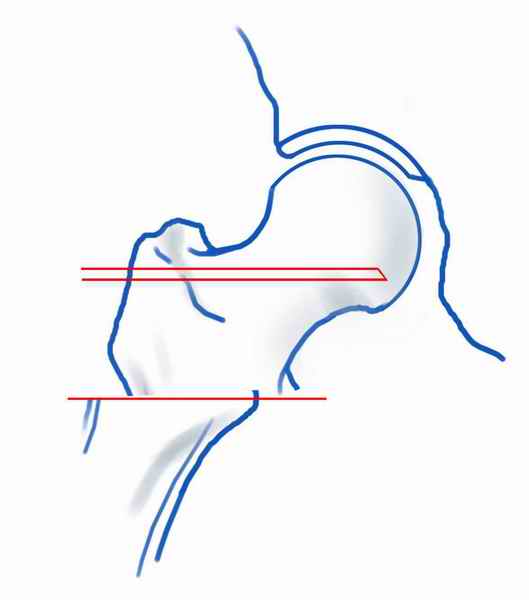

При явно выраженном варусе и флексионных состояниях после сросшихся переломов шейки бедра у молодых рекомендуется реконструктивная операция по исправлению варуса для предотвращения раннего деформирующего артроза, приводящего в результате переднего импинжмента, как показано на снимке.

Межвертельная вальгусная остеотомия представляет наименьший риск среди всех реконструктивных операции в проксимальной части бедра, создавая наилучшие биомеханические условия (увеличивается сила абдукторов, увеличивается сила суставной реакции, уменьшение рычага моментов абдукторов и уменьшение скольжения) и при меньшем риске повреждения кровоснабжения головки, где обычно в 90% случаях достигается отличный результат при применении метода для лечения ложных суставов шейки бедра.

По моему, 120 градусная угловая пластина blade plate решит все проблемы, только необходим предварительный расчет угла остеотомии, и во время фиксации пластины не забыть латерализацию бедра, иначе ось конечности от варуса перейдёт в нежелательный вальгус.

Для предупреждения вальгуса клинок пластины берется на 10-12 мм длиннее чем предварительный туннель на головке, тогда во время

фиксации за бедро пластина автоматически приблизит бедро и происходит латерализация бедра. Если между клинком и латеральным кортексом бедра положить частицу кости от остеотомии тогда образуется дополнительная компрессия на фокусе несращения.

Здесь мои диаграммы для расчета угла остеотомии и латеризации бедра.